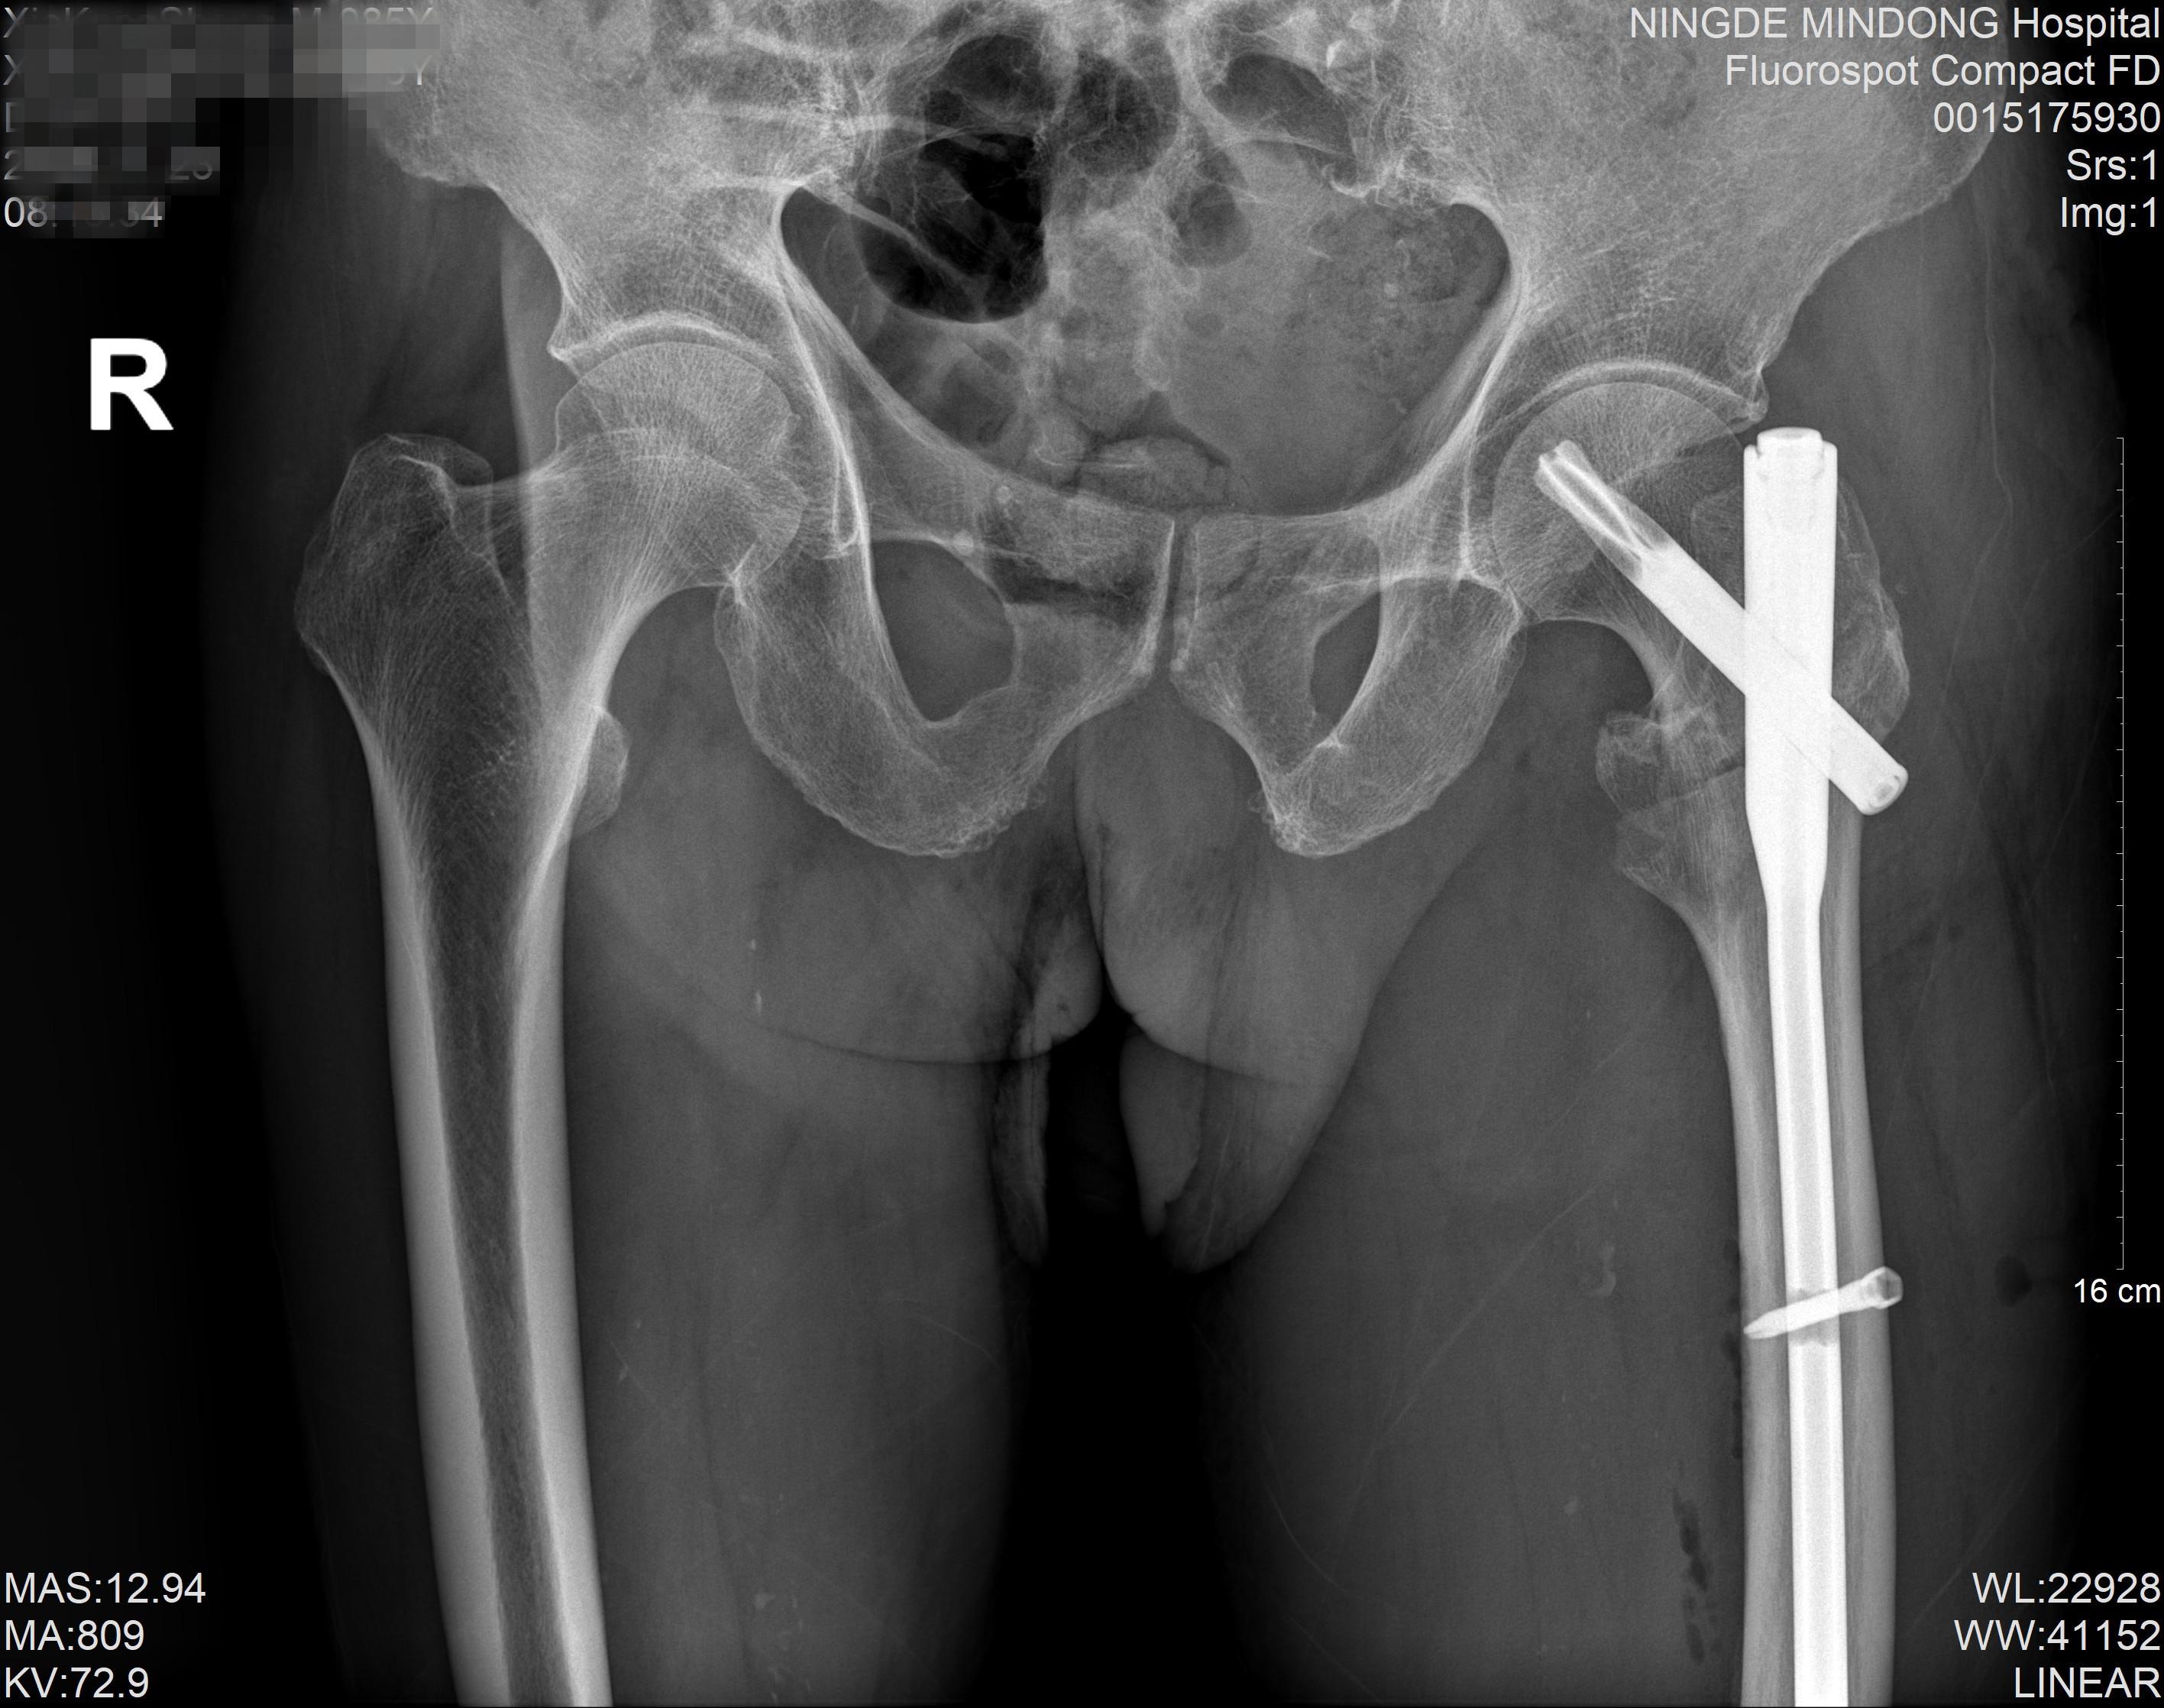

术后

近日,霞浦县一位85岁高龄的谢大爷,因摔伤导致左髋部剧痛、无法活动,于伤后第二天前往宁德市闽东医院就诊,被确诊为“左侧股骨粗隆间骨折”。创伤骨科何晓宇主任医师与张中宁副主任医师团队,为其实施了“左侧股骨粗隆间骨折闭合复位PFNA内固定术”。整台手术耗时约一小时,术中出血量仅约20毫升,展现了微创手术的优势。令人欣喜的是,术后第一天患者便能自行坐起,第二天即可站立,第三天已在助行器辅助下开始行走,恢复迅速。